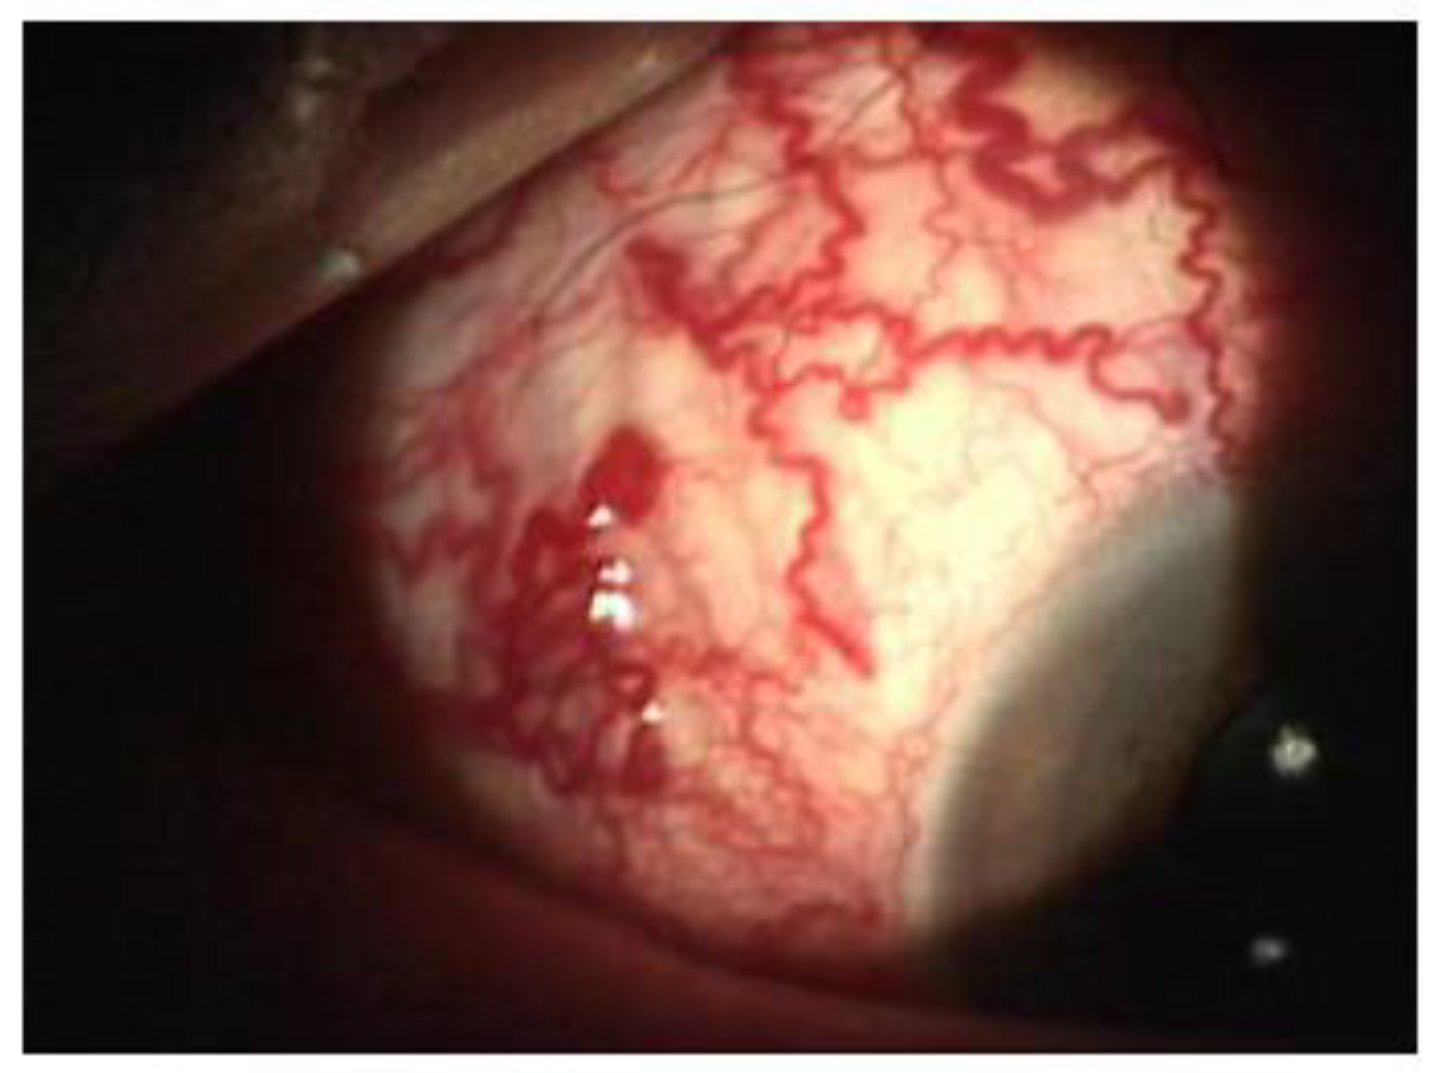

The multidisciplinary team involved in this case comprised neurosurgeons and interventional neuroradiologists. The treatment decided was carried out two times; the first provided the insertion of a cannula needle in the right orbital vein by a trans-palpebral anterior approach, while the second provided for the embolization of the cavernous sinus seat of the venous part of the fistula, through the placement of 5 spirals (Vortex 2x5, Boston), up to the complete exclusion of the fistula. The angiographic control performed immediately after the affixing of the spirals showed the complete normalization of the circulation between the internal and external carotid (Figure 6).

On the third post-operative day, the clinical condition was significantly improved in the following ways: a clear reduction of the exophthalmos and the congestion of the episcleral vessels (Figure 7), a complete recovery of ocular motility (Figure 8), visual acuity improved to 10/10, IOP was 14 mmHg, the disappearance of cotton exudates, and a normalization of the A/V ratio. Fifteen days after the surgery, the ocular conditions were stable.

Figure 6. The selective cerebral angiography revealing a dural fistula of the right cavernous sinus.